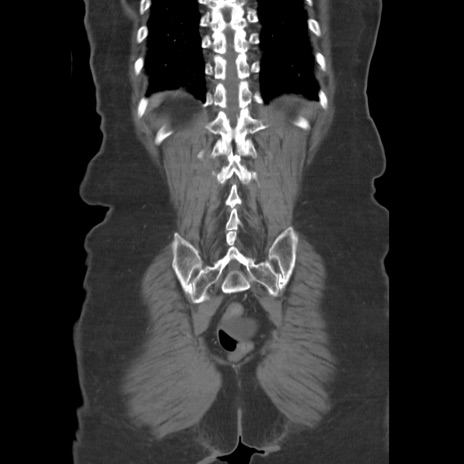

症例19(冠状断像)

【症例】80歳代女性

【主訴】下腹部痛

【現病歴】約8時間前より下腹部痛の出現あり、救急外来受診。

【既往歴】両側付属器切除

【身体所見】意識清明、下腹部正中に手術痕あり、その部位に一致して圧痛と反跳痛あり。腸蠕動音は亢進。

【データ】WBC 9300、CRP 0.15